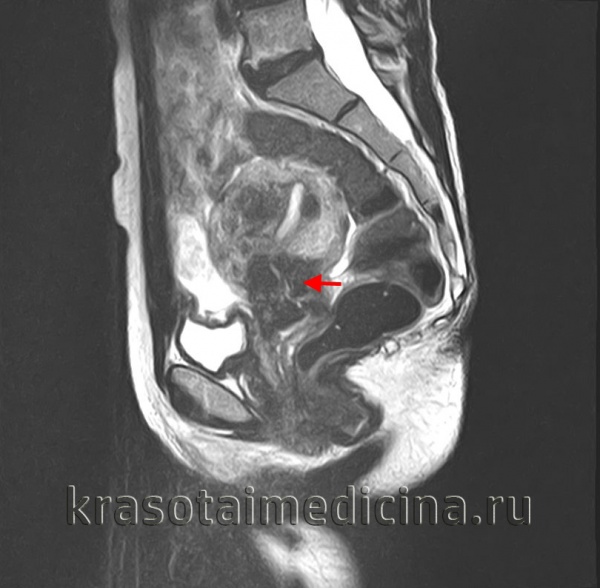

- МРТ с контрастированием. На сегодняшний день самый точный и информативный метод исследования мягкотканных органов. Данное исследование позволит оценить глубину опухолевой инвазии и переход злокачественного новообразования на параректальную клетчатку и смежные органы. При невозможности проведения МРТ, выполняется КТ с контрастированием.